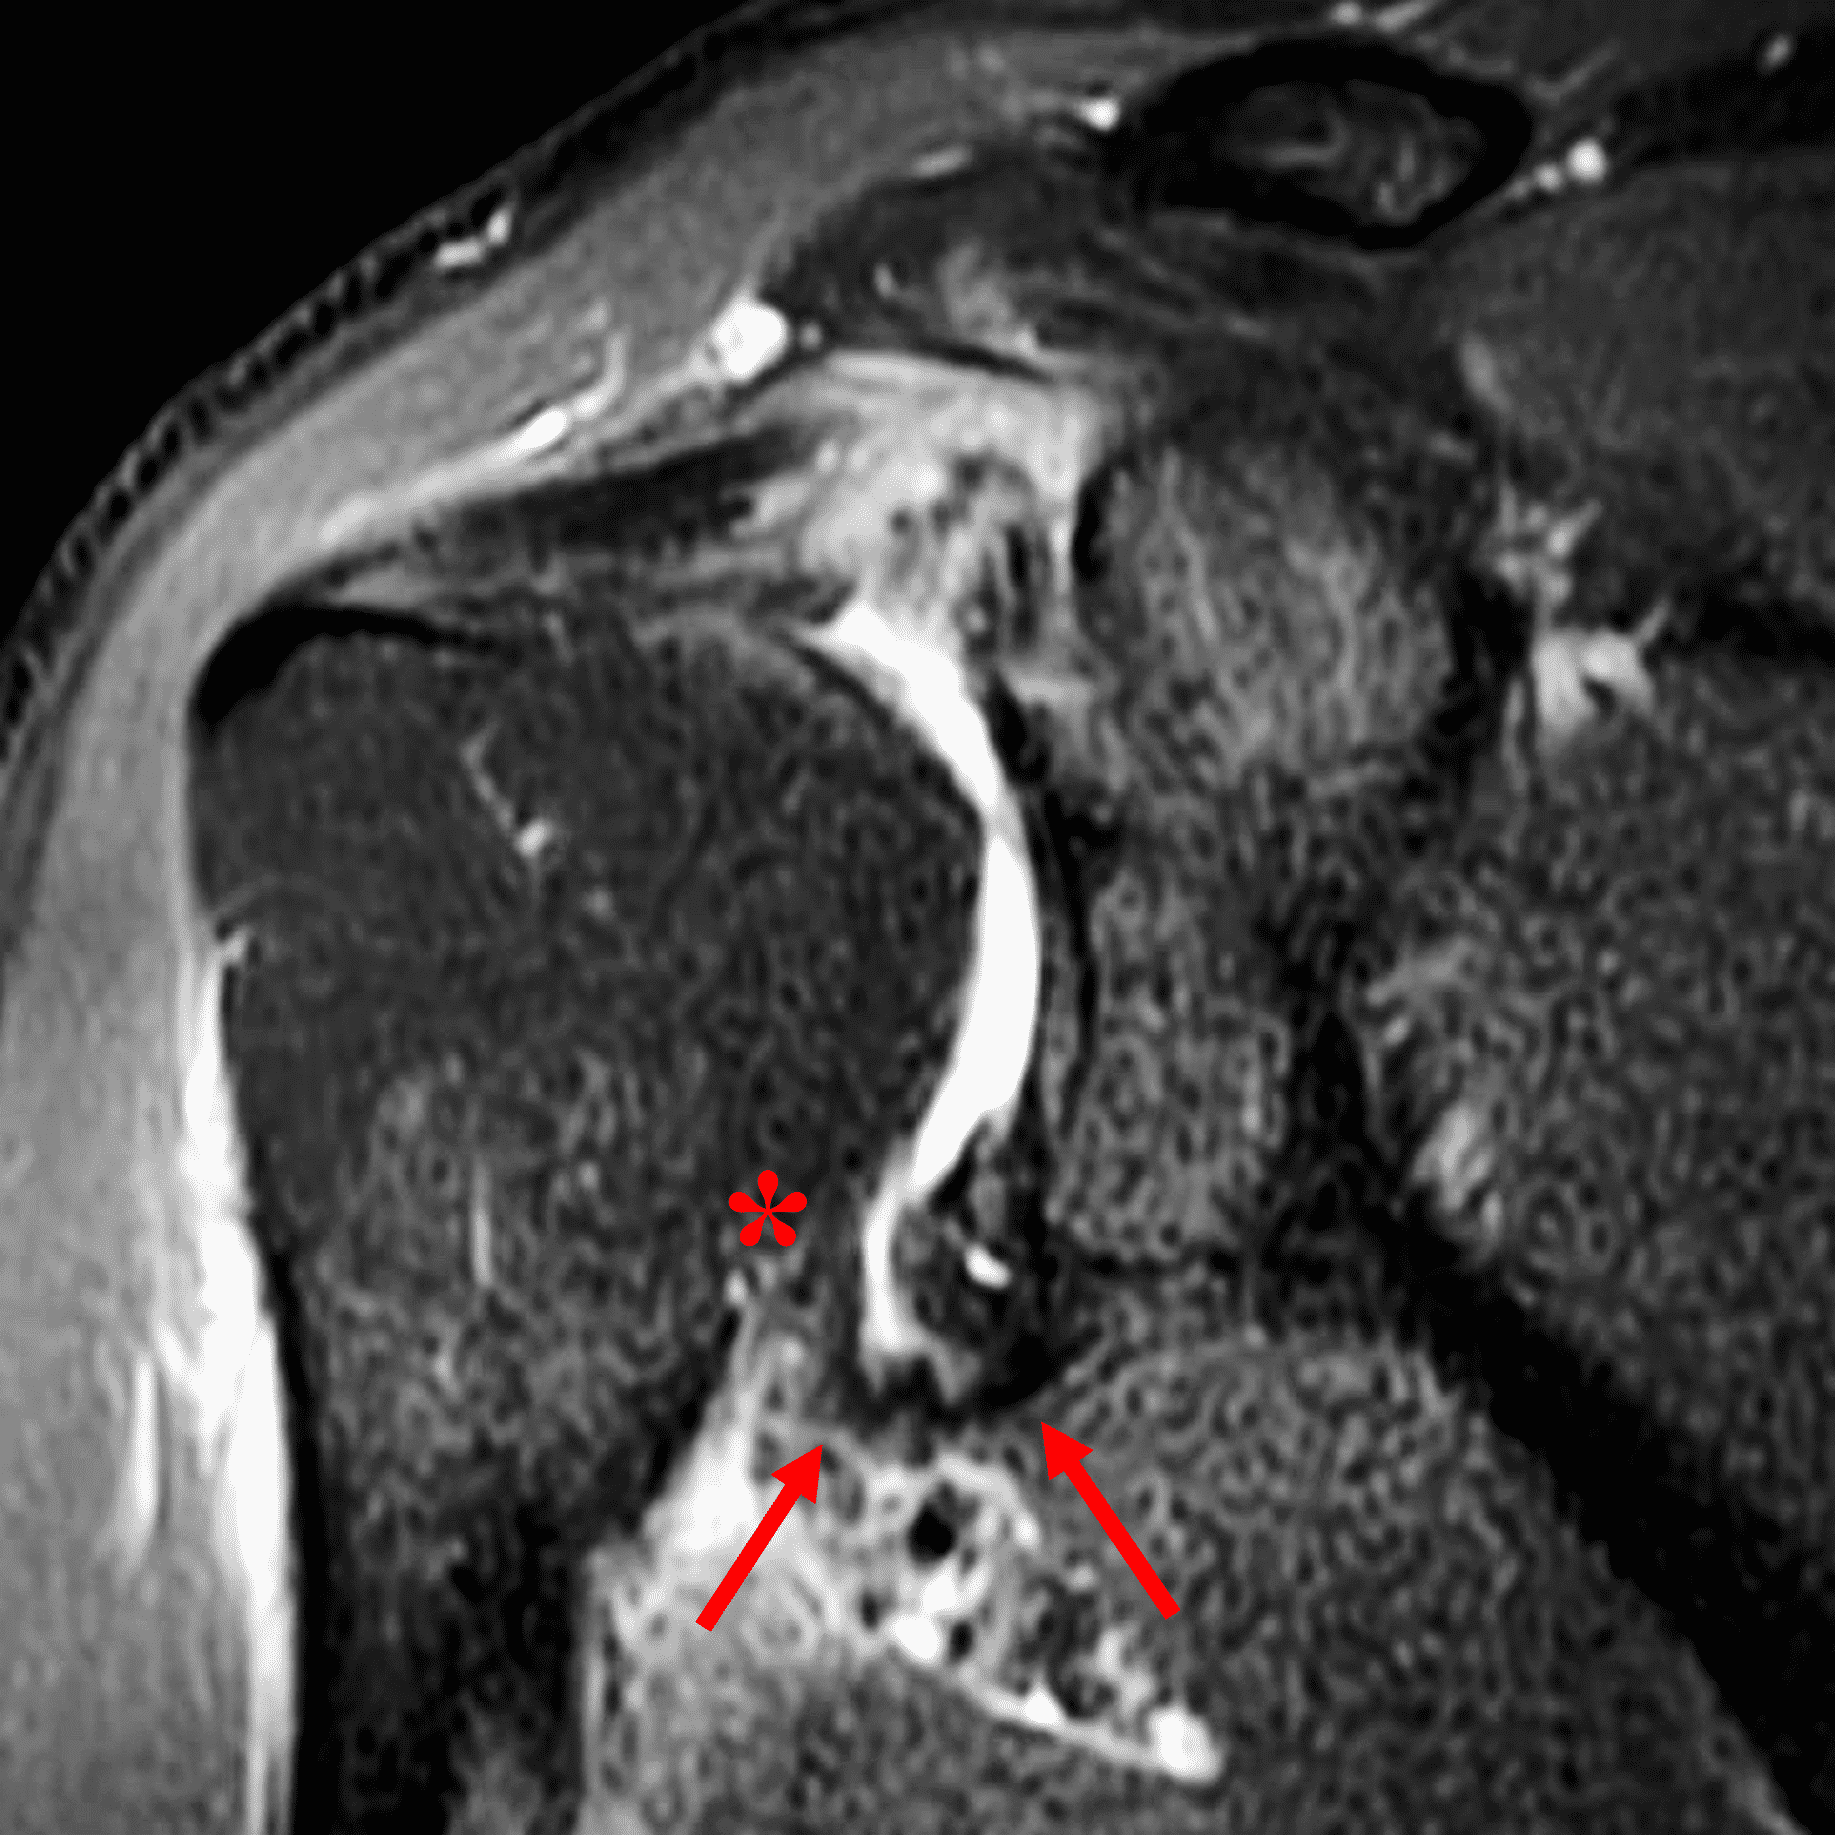

Figure 2: (2A) An axial image at the level of the humeral lesser tuberosity (LT) shows an intact subscapularis tendon (arrowheads). (2B) More inferiorly at the level of the humeral neck (HN), the direct muscular attachment of subscapularis (yellow arrows) is avulsed from the humerus together with the anterior band of the inferior glenohumeral ligament (red arrow), representing humeral avulsion of the glenohumeral ligament, a HAGL lesion. (2C) A coronal image through the anterior humerus shows the avulsed direct muscular attachment of subscapularis (yellow arrows), and the retracted end of the torn anterior band of the inferior glenohumeral ligament (red arrow). (2D) The radiograph shows a small, avulsed bone fragment of the humerus (red arrow), making this injury a “bony” HAGL (BHAGL) lesion. He failed 3 weeks of conservative management, with persistent 7/10 shoulder pain and was managed operatively with a lesser tuberosity repair. 6 months later, after taking a hiatus from baseball, his pain was completely resolved.

A pattern of injury has recently been described in pitchers and forceful ball throwers, who can injure the inferior subscapularis with sparing of the upper subscapularis muscle and tendon, like in the test case (Figures 1 and 2).20 A retrospective review of MRI scans from a Major League Baseball organization over a 5 year period identified 11 of 133 MRIs with subscapularis injury, 10 of which showed injuries occurring in the inferior half of subscapularis at the myotendinous junction, with sparing of the tendon.21 These inferior myotendinous injuries can extend to involve the direct muscular attachment at the humerus.

On MRI, injuries to the direct muscular attachment can manifest with edema and hemorrhage within the muscle and surrounding soft tissues, and/or avulsion of the muscle from the humerus. The lower signal intensity of the anterior band of the IGHL allows it to be distinguished from the direct muscular attachment of subscapularis, which can be important if the anterior band is torn and retracted (Figure 18). In these cases, the muscle tissue should not be mistaken for an intact IGHL. Hematomas may occur with injuries of the direct muscular attachment and can become quite large as they expand within the axillary soft tissues (Figure 19).